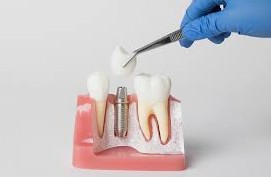

1. 임플란트는 왜 비쌀까?

치아가 빠지면 음식을 씹는 것도 불편하고, 외모나 건강에도 큰 영향을 줍니다. 그런데 임플란트는 일반적으로 한 개당 150만 원에서 300만 원 정도로 가격이 만만치 않습니다. 그래서 많은 시니어 분들이 치과 치료를 미루곤 하셨죠. 앞으로는 더 이상 미루지 말고 가까운 치과에 방문하여 상담받으시는것을 권장합니다. 임플란트 건강보험은 정부가 드리는 효도 선물 입니다.